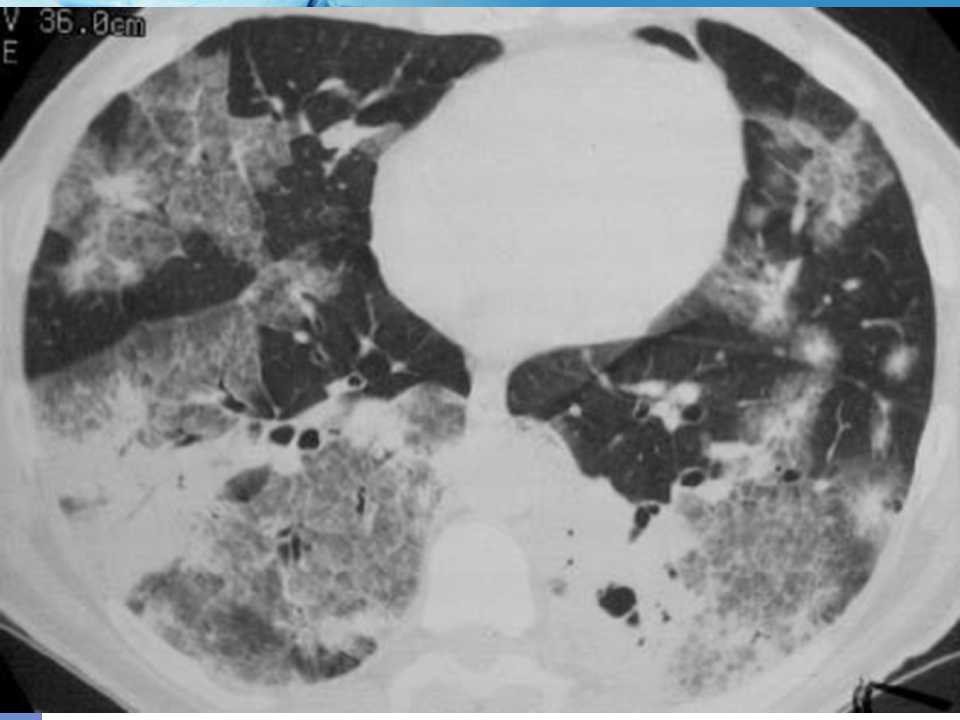

肺癌影像诊断